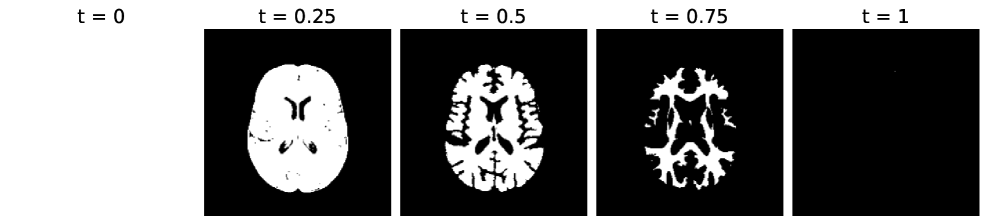

Both filtrations are illustrated in Fig. 6 on a T2 MRI of a healthy brain. We use the SRI24 Atlas [108] as a human brain anatomy reference.

The parameter of a filtration is to be understood as a temporal value: the more it increases, the more pixels are added to the image. In the case of sublevel sets, pixels of low intensity are added first. In Fig. 6a, these are the background pixels (filtration value ). On the contrary, in a superlevel set filtration, pixels of high intensity are added first. In Fig. 6b, we see that this corresponds to the ventricles and the grey matter. In other words, the most luminous parts of the image appear the earliest in filtration. This idea will be used in Section 4 when devising a segmentation method for glioblastomas. Indeed, on a FLAIR-modality MRI, glioblastomas tend to be represented by pixels of high intensity, hence we expect the tumor to be the first element to appear. This phenomenon is illustrated in Fig. 6c.